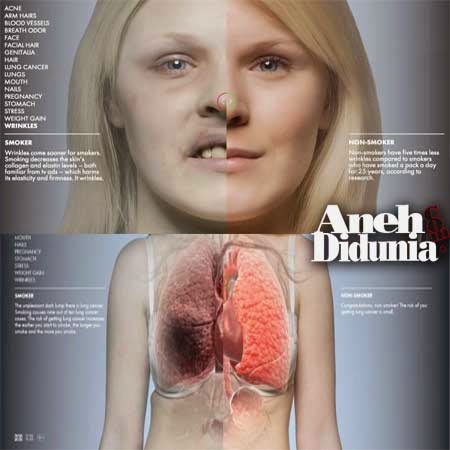

6 Dampak Dari Merokok Terhadap Perubahan Fisik Wajah Dan Tubuh

6 Dampak Dari Merokok Terhadap Perubahan Fisik Wajah Dan Tubuh

6 Dampak Dari Merokok Terhadap Perubahan Fisik Wajah Dan Tubuh

6 Dampak Dari Merokok Terhadap Perubahan Fisik Wajah Dan Tubuh